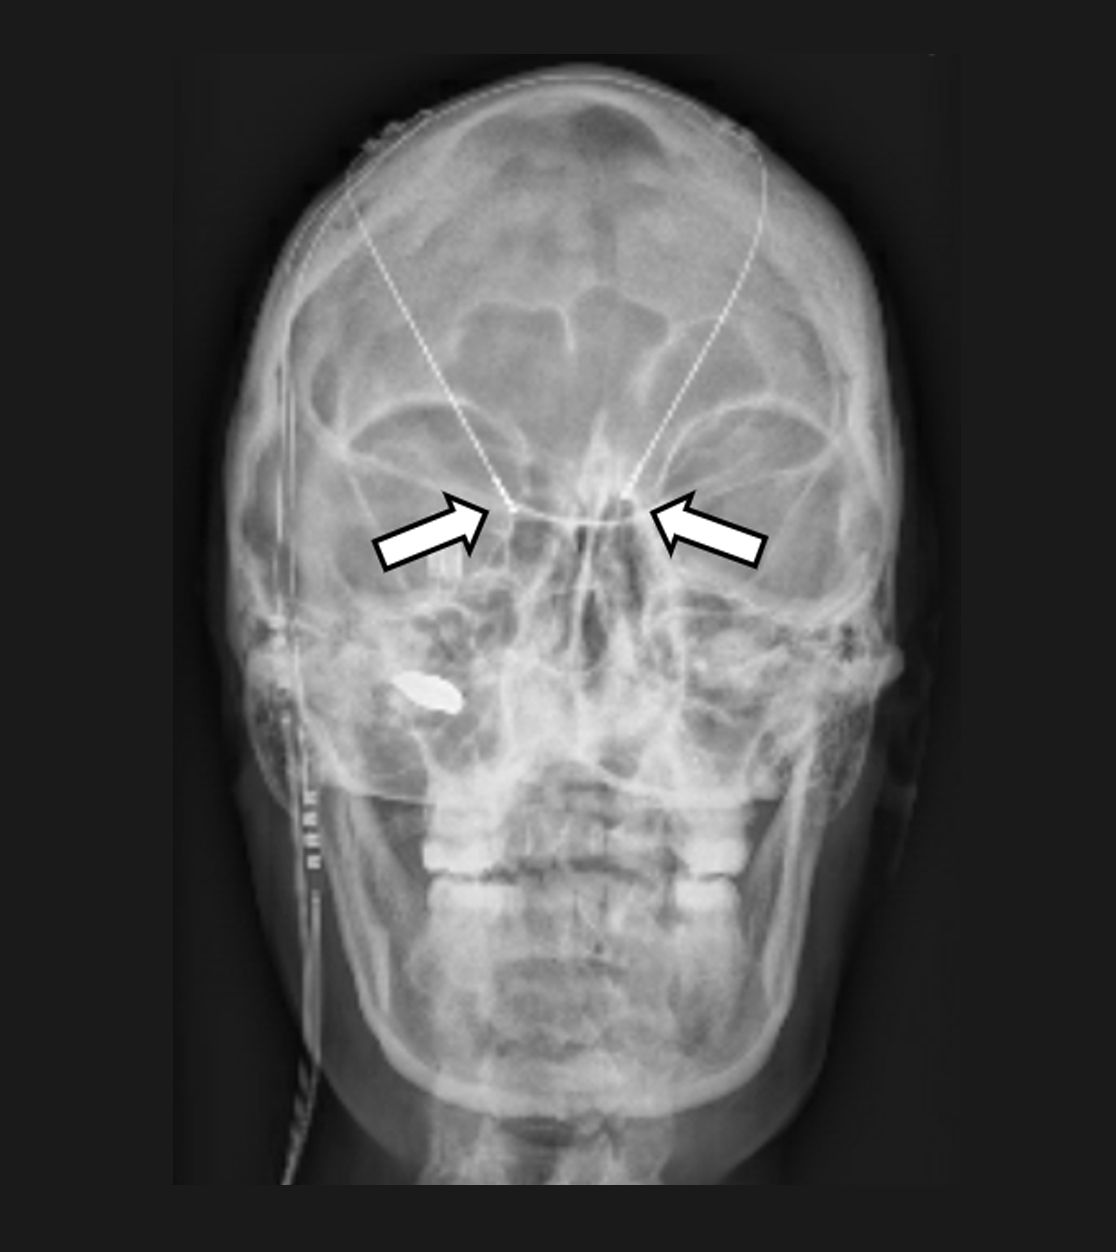

In das Gehirn implantierte Elektroden zur Tiefen Hirnstimulation (Pfeile)